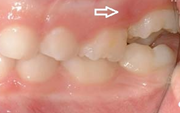

Esimeste molaaride (purihammaste) lõikumine

Esimeste molaaride (purihammaste) lõikumine. 1. molaaride ektoopilise lõikumise jälgimine. Ülemised ja alumised esimesed purihambad e. molaarid lõikuvad orienteeruvalt6-7-aastaselt piimahammaste rea lõppu. Enamasti lõikuvad samanimelised jäävhambad paaridena. Normaalne lõikumise Loe edasi »

Sümptomid:

- valehambumus (18)